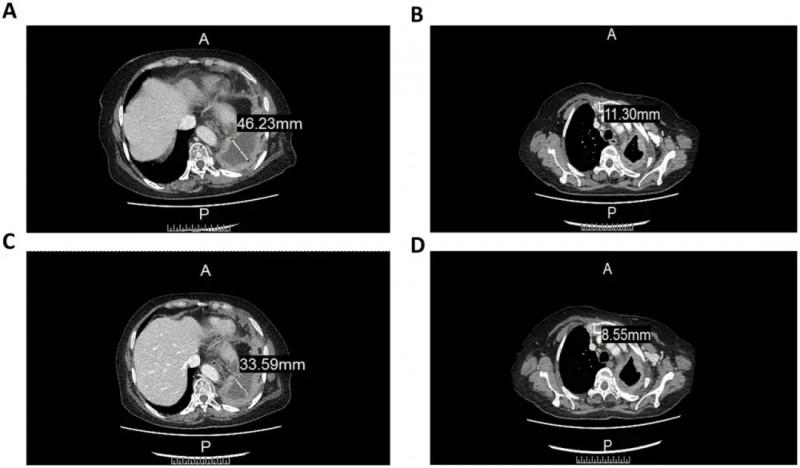

结果显示:治疗后CT检查发现肿瘤病灶显著缩小、胸腔积液也有所减少。具体表现为前气管-后腔静脉间质区淋巴结由11.3mm缩小至8.55mm(详见下图B/D),左肺包裹性胸腔积液由46.22mm减少至33.59mm(详见下图A/C)。

▼CCCR-NK92细胞治疗前后CT图像对比

▲图源“Sage Journals”,版权归原作者所有,如无意中侵犯了知识产权,请联系我们删除